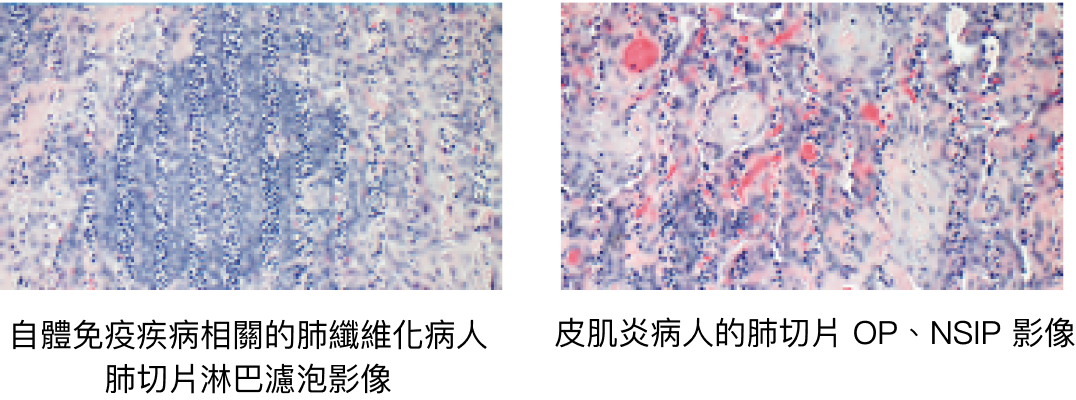

肺切片檢查3

並非所有電腦斷層影像都能被精確歸類,判別是否具有肺纖維化,有時仍需進行切片以確立診斷。切片方式可分為8:

• 手術切片 (胸腔內視鏡輔助手術 / 開胸手術)

• 支氣管鏡切片 • 支氣管鏡冷凍切片

• 切片的病理組織報告包含了 NSIP、UIP、OP 及瀰漫性肺泡損傷 (DAD):

自體免疫疾病相關的肺纖維化病人 HRCT 檢查結果中,最常出現非特異性間質性肺病 (NSIP) 及尋常性間質性肺病 (UIP) 的影像,較少出現器質性肺炎 (OP) 的影像。

• 硬皮症病人的影像結果較常出現 NSIP,而 UIP 則可見於 40% 的硬皮症病人。

• 多發性肌炎及皮肌炎病人的影像結果較常出現 NSIP 與 OP 的重疊影像。